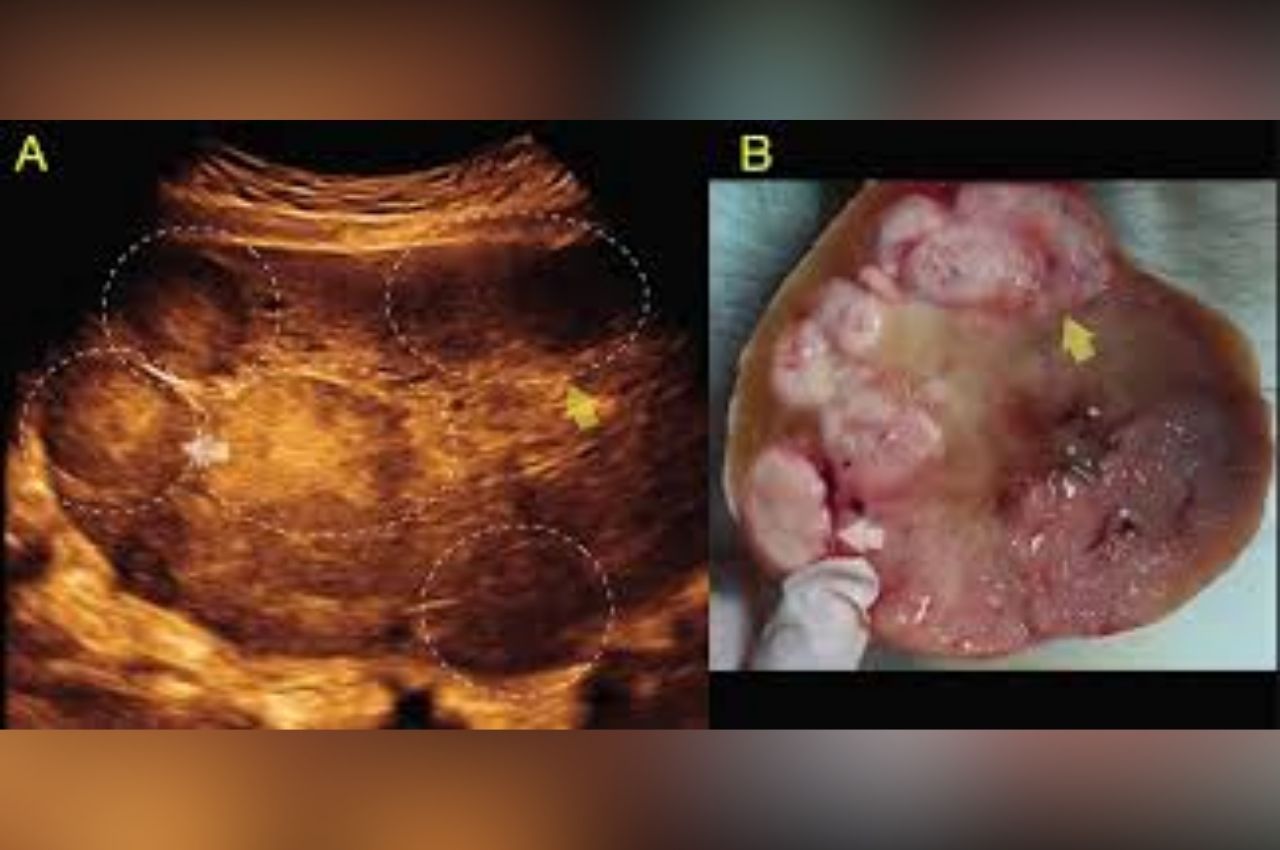

Mengenal Disgerminoma: Kanker Sel Germinal pada Wanita Muda

Disgerminoma mungkin terdengar asing bagi sebagian besar orang, namun dalam dunia medis, ini adalah jenis kanker